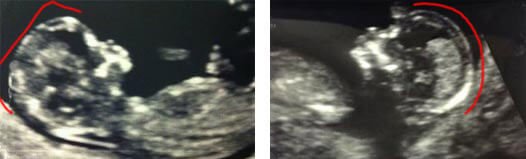

The Nub theory, also known as the “angle of the dangle” proposes that the gender of a child can be known by analyzing the nub angle and shape. During the early stage of pregnancy, a major feature in male and female fetuses is a genital tubercle which develops into the male penis and the female clitoris in later stages. This is referred to as the nub.

In order to view the nub in relation to the spine, it must be scanned in profile view. In a situation whereby the nub is located at an angle exceeding 30 degrees in relation to the spine, then there is a likelihood that we have a male fetus but in a situation whereby the nub is below 30 degrees and pointing straight, then there is a possibility the fetus is a female.

When scans were carried out in a controlled setting, some of the studies’ predictions reflected 88% accuracy at 12 weeks gestation. Experts on gender determination have carried out findings on three study groups and the level of accuracy of the Nub theory collected ranged between 80-92% for model visibility nub scans.